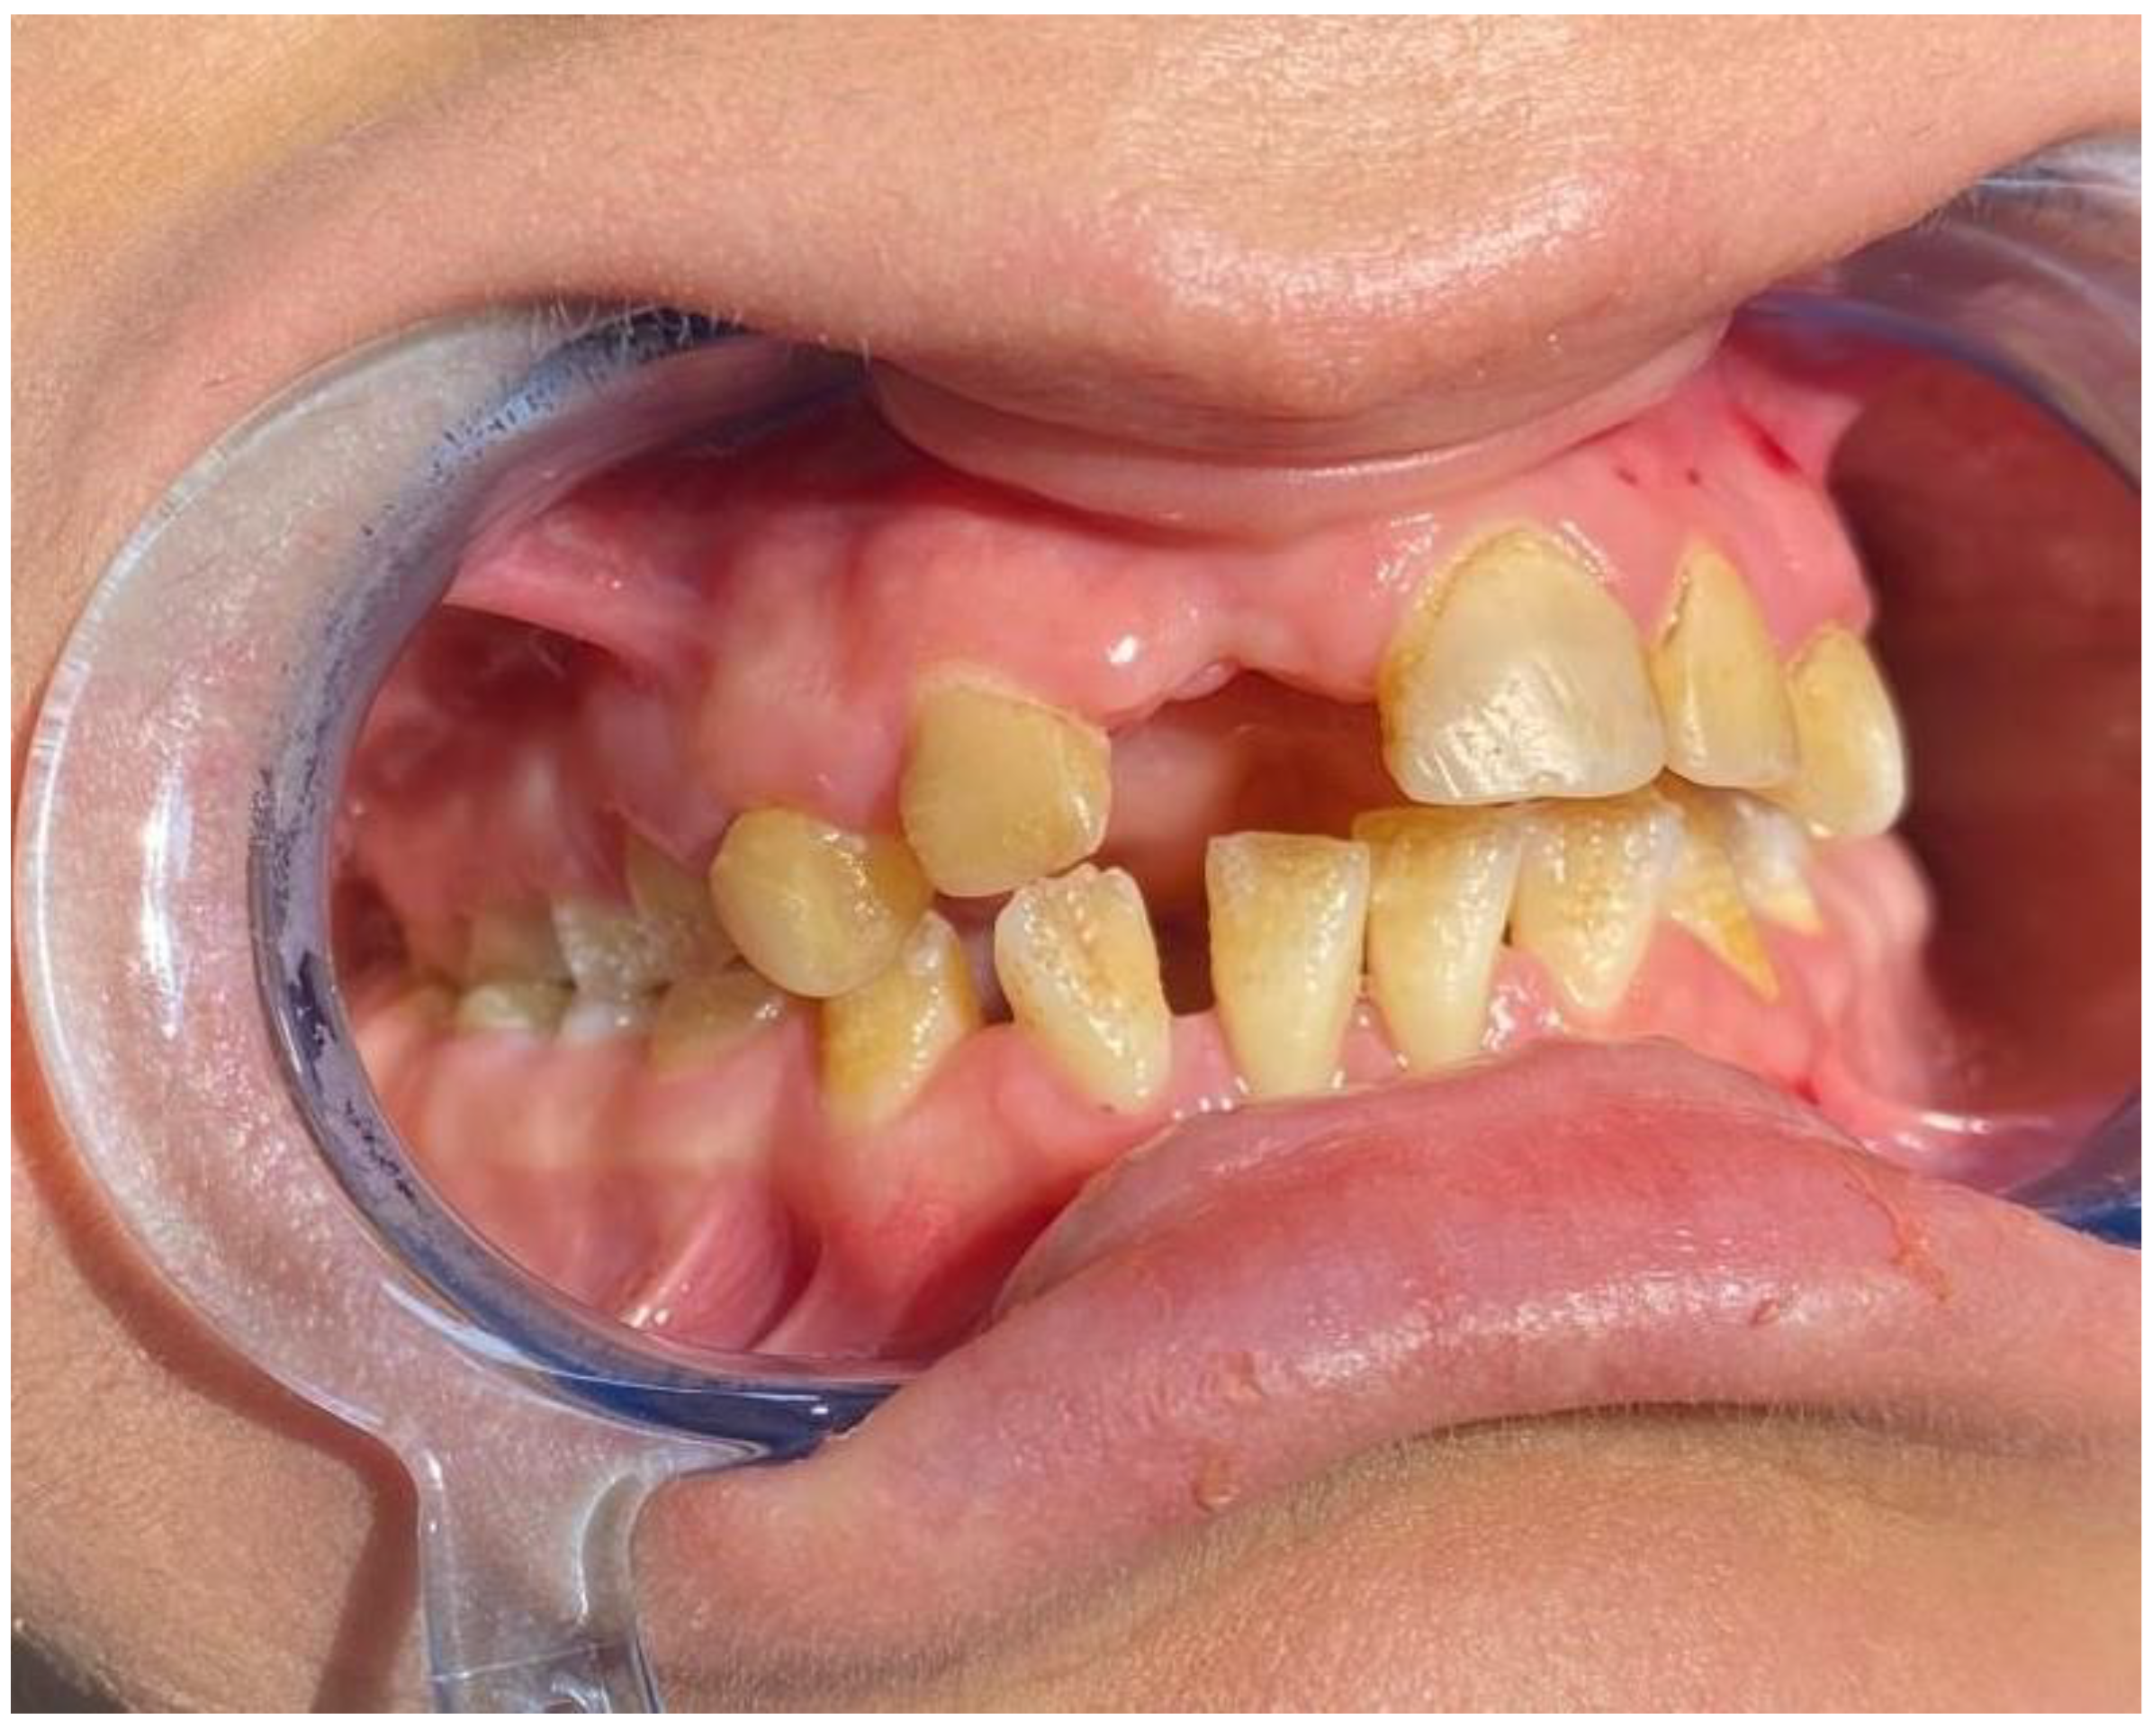

When the intraoral findings of the patients were investigated, extensive dental caries, enamel hypoplasia in JEB and presence of tooth-root to be extracted in DEB, intraoral bullae and lesions in 92%, ankyloglossia and vestibular sulcus insufficiency in 73%, and microstomia and maxillary atrophy in 69% were observed in all EB types (Figure 2, Figure 3 and Figure 4). In three cases, treated tooth restorations were seen, and in one case, fixed prosthetic zirconium restoration was seen. General clinical findings reported according to EB type are shown in Table 1, and oral findings are shown in Table 2.

Figure 3.

Common dental caries and tooth to be extracted.